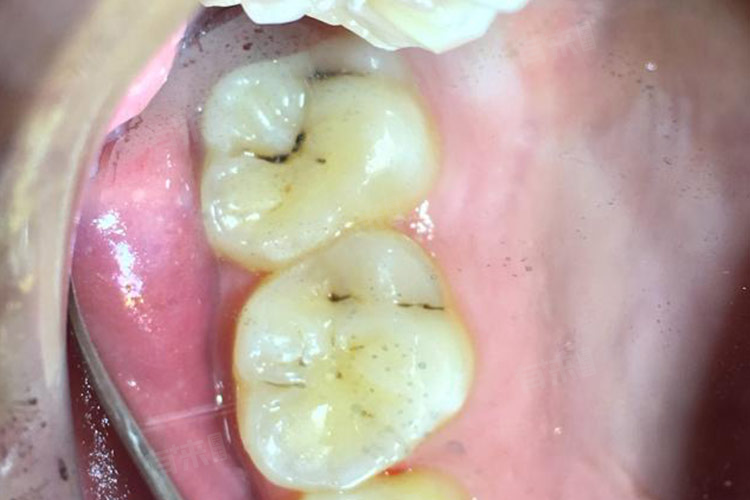

4、龋齿:

龋齿(蛀牙)由细菌分解食物残渣产生酸性物质,腐蚀牙釉质和牙本质,形成龋洞,龋洞内的腐败坏死组织和色素沉积呈黑色,表现为牙齿表面的黑色斑点或凹陷。初期黑斑较浅,随病情进展龋洞扩大,累及牙髓时引发疼痛,若不及时治疗,会导致牙冠破坏、牙齿脱落,是儿童和青少年牙齿黑斑的主要原因。